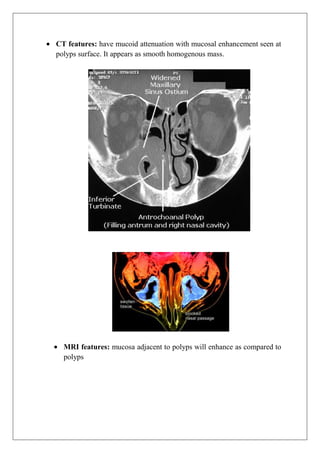

CT features: have mucoid attenuation with mucosal enhancement seen at

polyps surface. It appears as smooth homogenous mass.

MRI features: mucosa adjacent to polyps will enhance as compared to

polyps